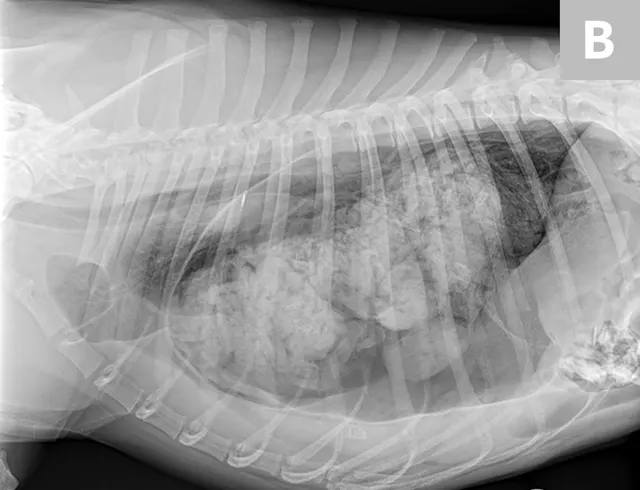

FIGURE 5A

(A) Dorsoventral and (B) right lateral radiographs of a 1-year-old spayed dog with acute-onset respiratory distress resulting from gastric dilatation in the left pleural cavity. The dog had a history of trauma approximately 1 month before presentation. The stomach is dilated, and a large amount of gas and food content can be seen in the left hemithorax

Based on recent reports, definitive surgical repair (ie, herniorrhaphy) can be performed as soon as the patient demonstrates cardiovascular stability; previously, waiting at least 24 hours after presentation was recommended.2,3,6 However, patients with pulmonary contusions may benefit from delayed surgery, which can allow for resolution of pulmonary inflammation and hemorrhage (ie, contusions) and thus make the patient a better anesthetic candidate. Emergency surgery may be necessary in cases in which a herniated stomach distends (with or without volvulus) and results in respiratory distress that cannot be managed with thoracocentesis and/or oxygen support (Figure 5).7 In chronic diaphragmatic hernia patients, adhesions between abdominal contents and thoracic structures should be anticipated. In such cases, the surgeon should be prepared to perform a median sternotomy (following initial laparotomy) to improve exposure for adhesiolysis.